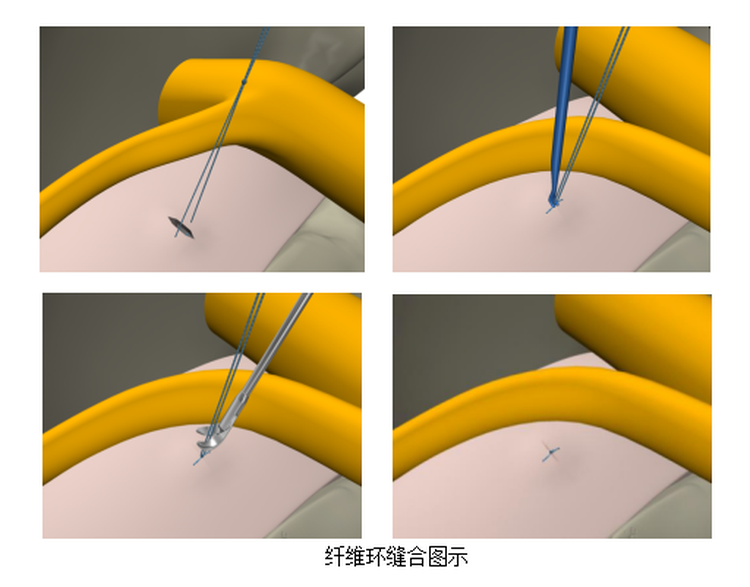

随着骨科技术的发展,腰椎间盘突出症已有很多先进的治疗方法,其中椎间孔镜下髓核摘除术是目前常用的一种行之有效的微创治疗方法。与传统手术相比,该手术具有手术创伤小,对术区周围组织损伤小,出血少,伤口小,可早期下地活动,安全性高等优点。但该手术方式存在术后椎间盘突出疾病复发的可能,为避免术后的再次复发,就需要将患者破损的纤维环进行缝合修复。

6月5日对患者行经椎板入路椎间孔镜下腰5骶1髓核摘除+纤维环修复术治疗。

此次椎间孔镜下纤维环缝合术的开展,有效降低了术后的复发率,使我院脊柱微创手术水平得到再一次提高,标志正我市在脊柱微创诊治领域达到了省级先进水平。